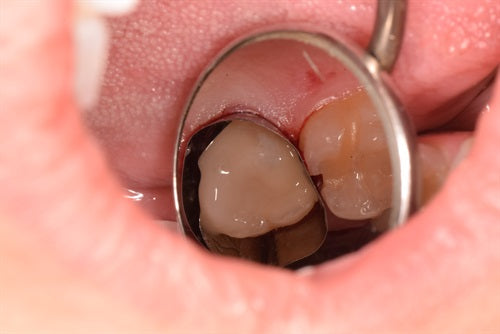

Class II Restoration on Lower Second Premolar

Introduction: This case was completed by Dr. Raul Costa, a Cosmetic and Restorative dentist, practicing at Wimpole Street Dental Clinic in London. You can see more of his work on... Read More